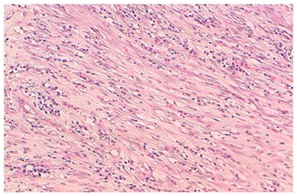

Figure 3 Spindle cells arrayed in fascicles, mixed with inflammatory cells (medium magnification).

The biopsy is necessary to confirm the diagnosis, which usually shows a combination of inflammatory cells and mesenchymal cells which mainly is the plasma cells, histiocytes, lymphocytes and spindle cells Pettinato et al.,5 has described IFT histologically to be a an inflammatory cells with proliferative myofibroblasts and fibroblasts, with IHC positive for vimentin and smooth muscle actin.6 The IMT can invade blood vessels but a rare occurrence, as it infiltrates the lung with the inflammatory cells, it is very difficult to differentiate as the normal lung architecture gets distorted. The imaging studies done at baseline was normal, but a repeat CT thorax was done showing pleural thickening with hyper inflated left lung and bronchiectatic changes multiple patchy areas of consolidation in bilateral lungs. PET-CT confirmed the findings with hyper-metabolic uptake in the bilateral supraclavicular areas. In our case the biopsy of the pleural thickening showed mixed areas of spindle cells interlaced with plasma cells and lymphocytes. IHC positive for smooth muscle actin, vimentin and ALK negative, confirming IMT.